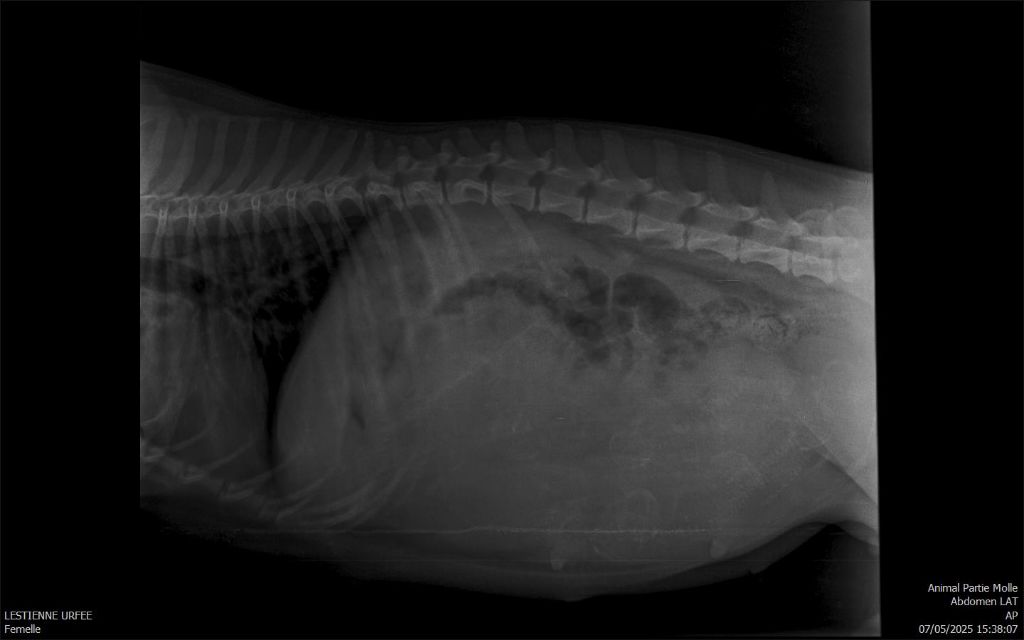

La radio de comptage a été réalisé mais étant de très mauvaise qualité difficile à dire combien de chiots seront à naître.

5 c'est sûre à voir à la naissance